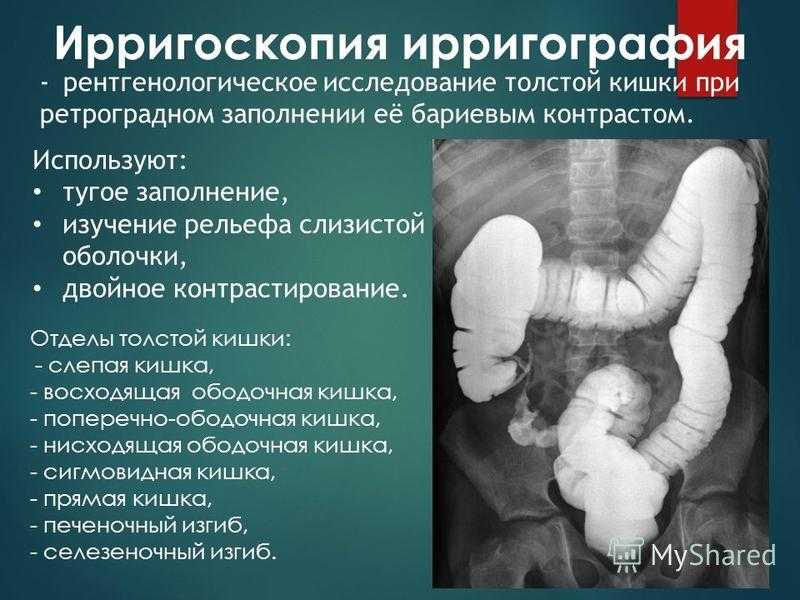

Рентгеноконтрастные Исследования Кишечника: Визуализация и Методики